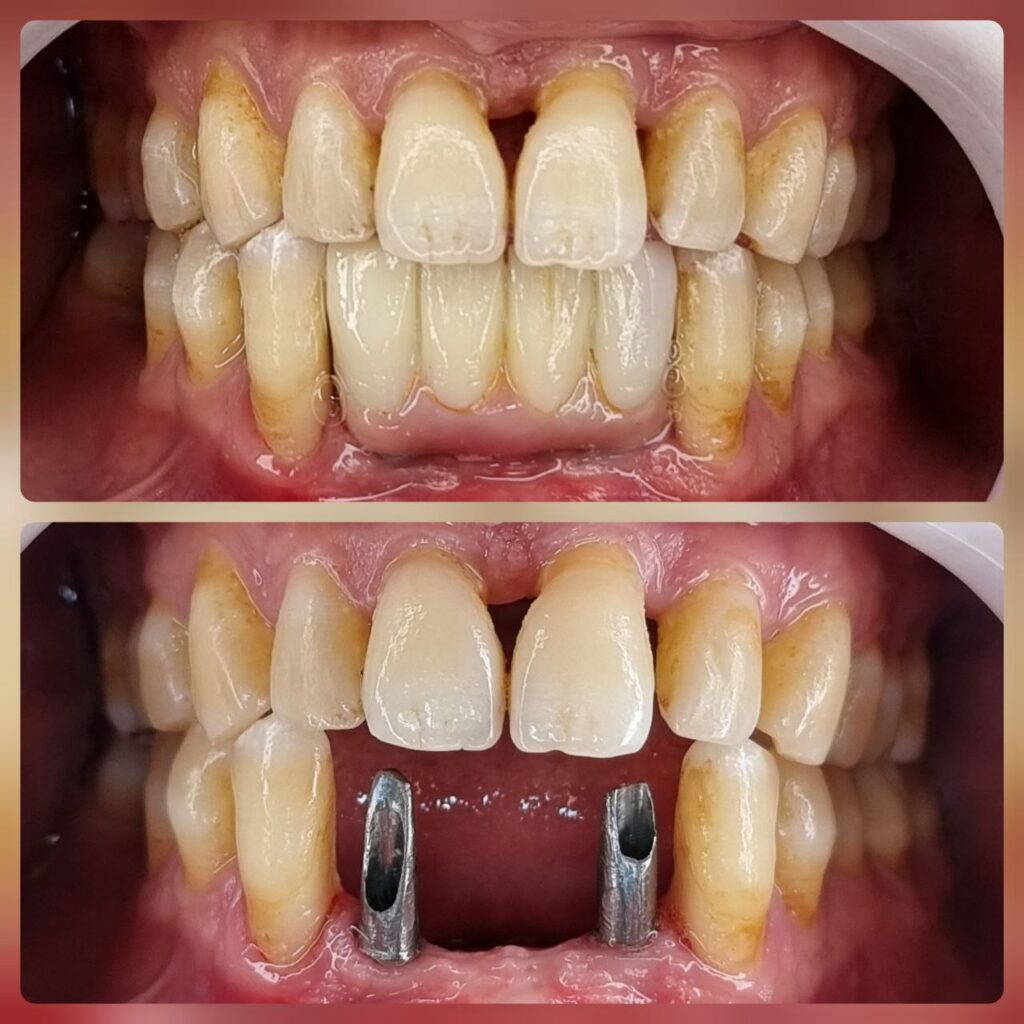

کاشت ایمپلنت دندان

اطمینان حاصل کردن از اینکه دندانهایتان به نحوی زیبا و طبیعی جایگزین شدهاند، از اهمیت بسیاری برخوردار است. ایمپلنت دندان به عنوان یک روش درمانی دائمی در دندانپزشکی شناخته میشود که حاصل آن، یک دندان زیبا و طبیعی در دهان شما خواهد بود.

هرچند که این روش درمانی هزینهی بیشتری نسبت به روشهای دیگر دارد، اما ارزش زیبایی که ایجاد میکند، قابل انکار نیست. ایمپلنتها به قدری شبیه به دندانهای طبیعی هستند که به سختی میتوان آنها را از دیگر دندانها تشخیص داد.